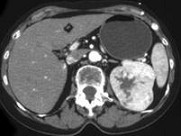

- 单项选择题男,54岁, 左侧腰痛伴间断性血尿2月余,结合CT图像, 最可能的诊断是 ( )

A、左侧肾癌

B、左侧肾血管平滑肌脂肪瘤

C、左侧肾上腺腺癌

D、左侧嗜铬细胞瘤

E、左侧肾盂癌